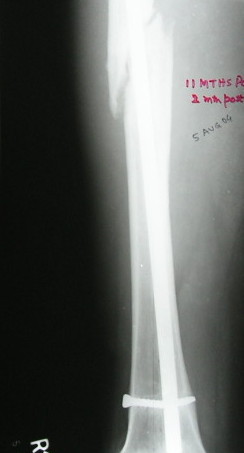

with the knee flexed. Pass the k wire into the lumen of the nail for a short distance. I am not sending the pictures to you to prepare a composite one, rather, send 3 or 4 mails each including one picture.

VMI-I am enclosing pictures of how I had to do it once. The C arm picture shows the first attempt to try and jam a solid reamer into the nail and trying to pull it out. Did not work.

The second picture shows a plain guide wire inserted thro the nail, prograde, hammered out thro the distal femur, out thro the skin. A beaded guide wire being railroaded on the earlier G W into the distal end of the nail.

This is the C-arm picture before attemting to pull out thro the proximal end by hammering on a chuck.

Did not work out. The nail was a slotted one. The guidewire split the slot and came out but not the nail. Ultimately as mentioned in an earlier mail, I had to introduce a cannulated nail from distally threadind on the guide wire and hammer on the stuck nail and finally got it out

This picture shows the beaded guide wire into the nail from its distal end.

V M Iyer